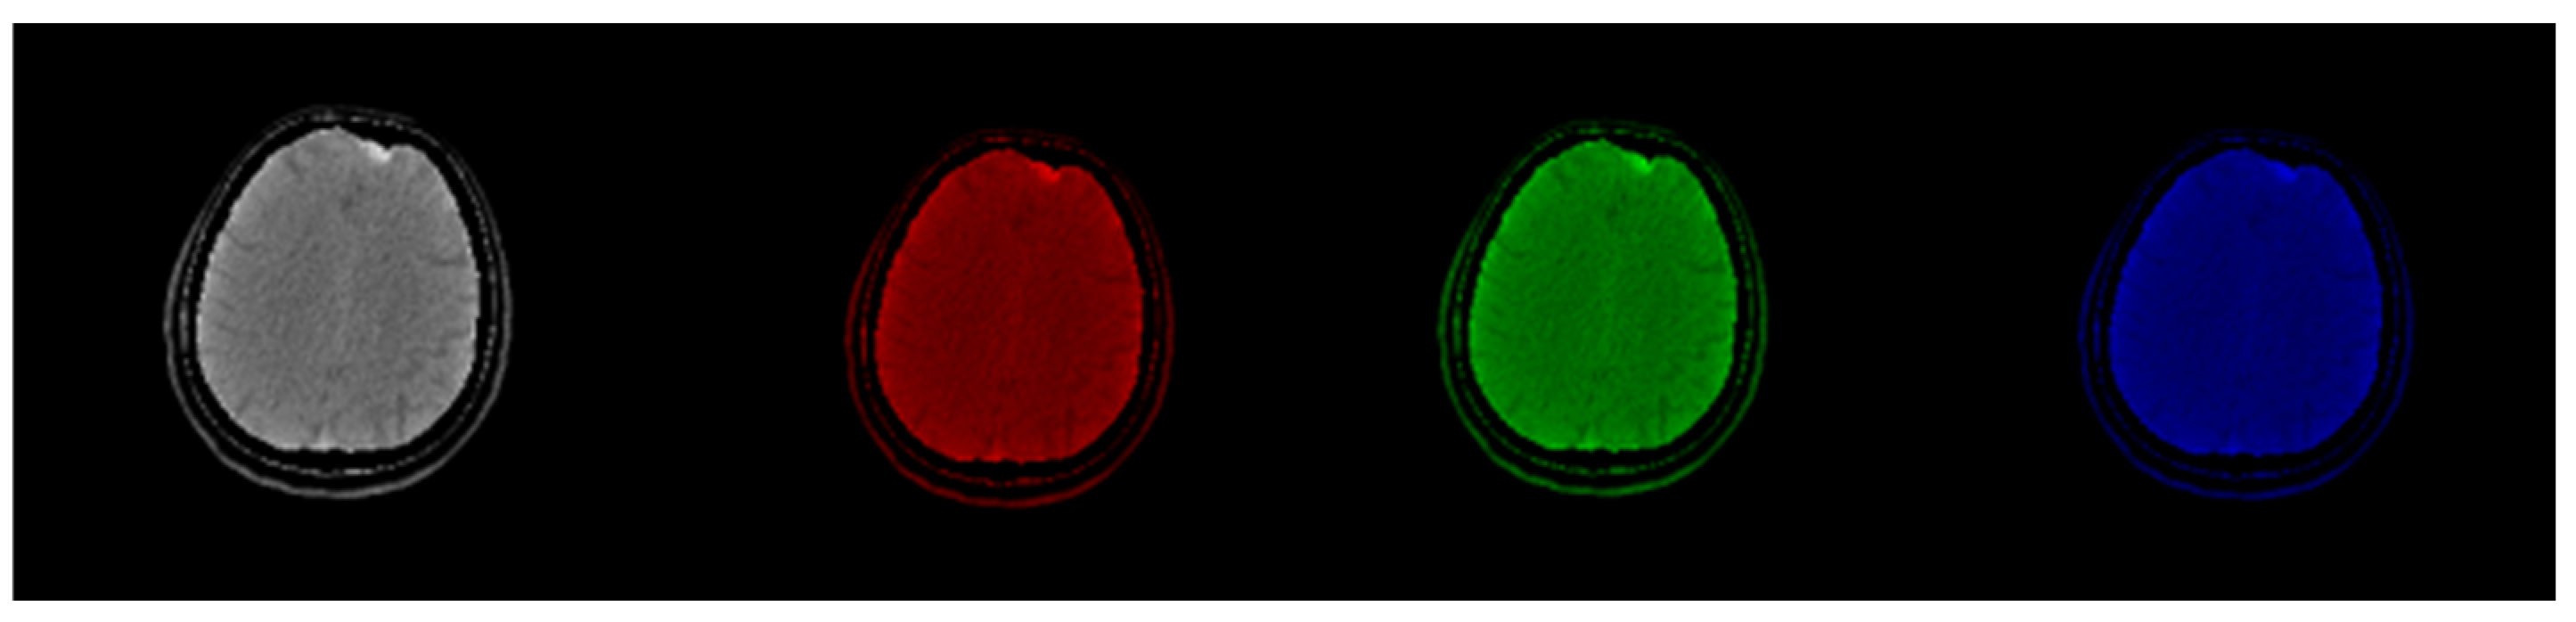

2.2. Method 1: Colormap Information Transform (CIT)

3.1. CIT Application